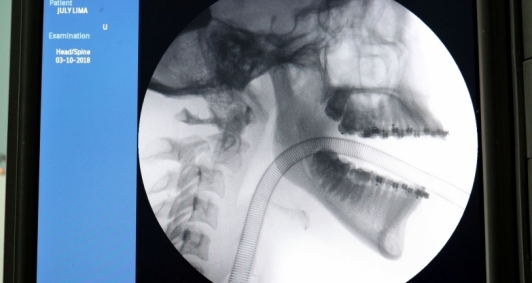

A Paciente, J. G., de 17 anos, foi vítima de acidente de motocicleta, resultando em politraumatismo. Possuía uma fratura no fêmur, já operada, e uma fratura na coluna cervical com bastante gravidade, conhecida como fratura do enforcado — uma fratura luxação C2 e C3.A paciente estava aguardando a cirurgia de fixação da coluna cervical, que, segundo Dr. Douglas, é uma cirurgia muito delicada. “No local se encontram os principais vasos da cabeça: carótida, artéria vertebral e medula. Por isso, é uma cirurgia que poucos profissionais realizam”, esclareceu o Neurocirurgião.

Além do alto risco cirúrgico, Dr. Ramon explica que a Artrodese entre as vertebras C1 e C3 por via posterior devido a fratura da vertebra C2, possui outra particularidade que dificulta sua realização, que é a utilização de material com dificuldade de acesso, principalmente na rede do SUS. “Utilizamos parafusos pediculares e de massa lateral, que são materiais que poucos hospitais dispõem, por ser um material muito caro e difícil de encontrar no mercado hospitalar”. A cirurgia de fixação da coluna cervical durou 5 horas e foi considerada um sucesso. A paciente se encontra em recuperação e está com quadro estável na UTI Cirúrgica do HEAA.